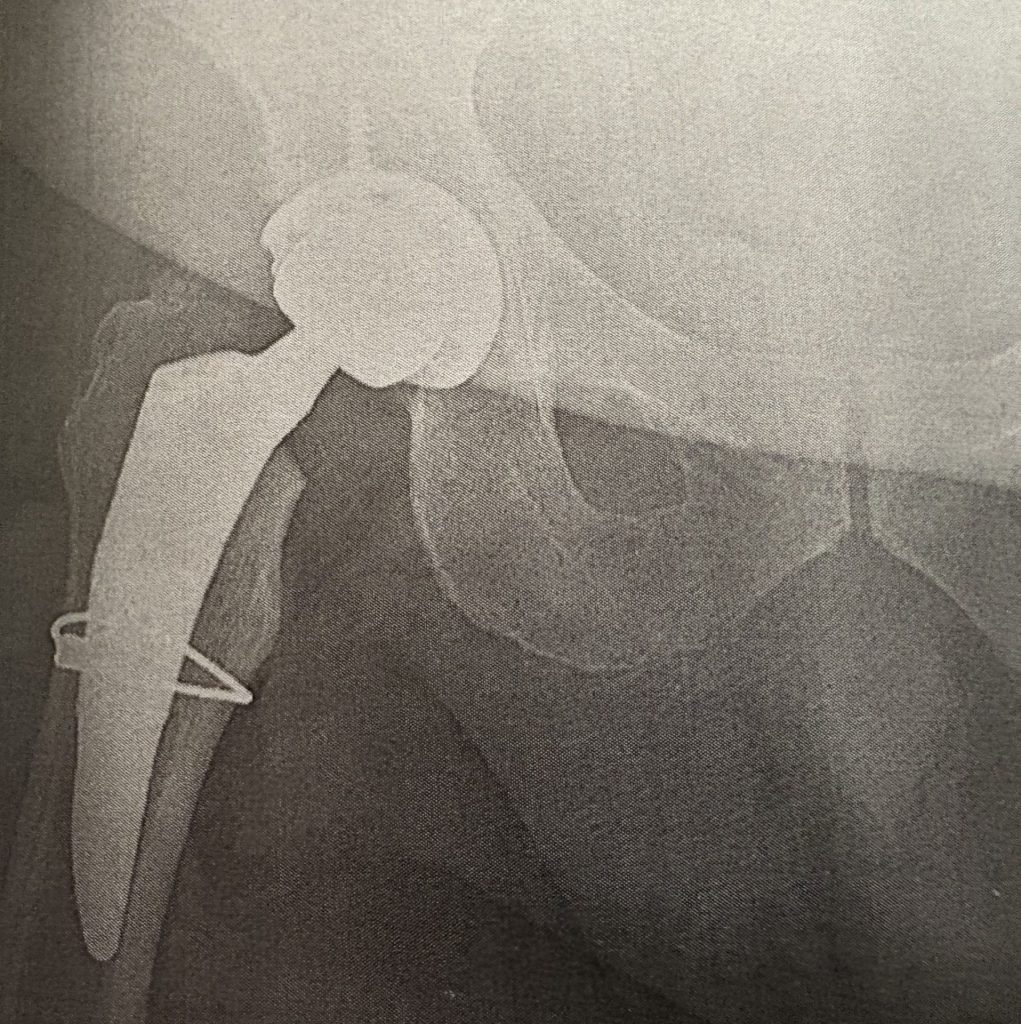

I had a progressive complex internal rotation deformity of my right femur head, which weakened the quality of my femur bone. I went to many doctors who would not take my case, however Dr. Carli provided impeccable care and research into my replacement with multiple conversations and tests to ensure he could complete the replacement correctly.

Going into the surgery, Dr. Carli explained the difficulty and possible issues we would face. Post-surgery, he explained the over-three-hour surgery in which he would use multiple apparatus to try to find the perfect fit for my replacement while consulting with colleagues to ensure he was doing the best job.